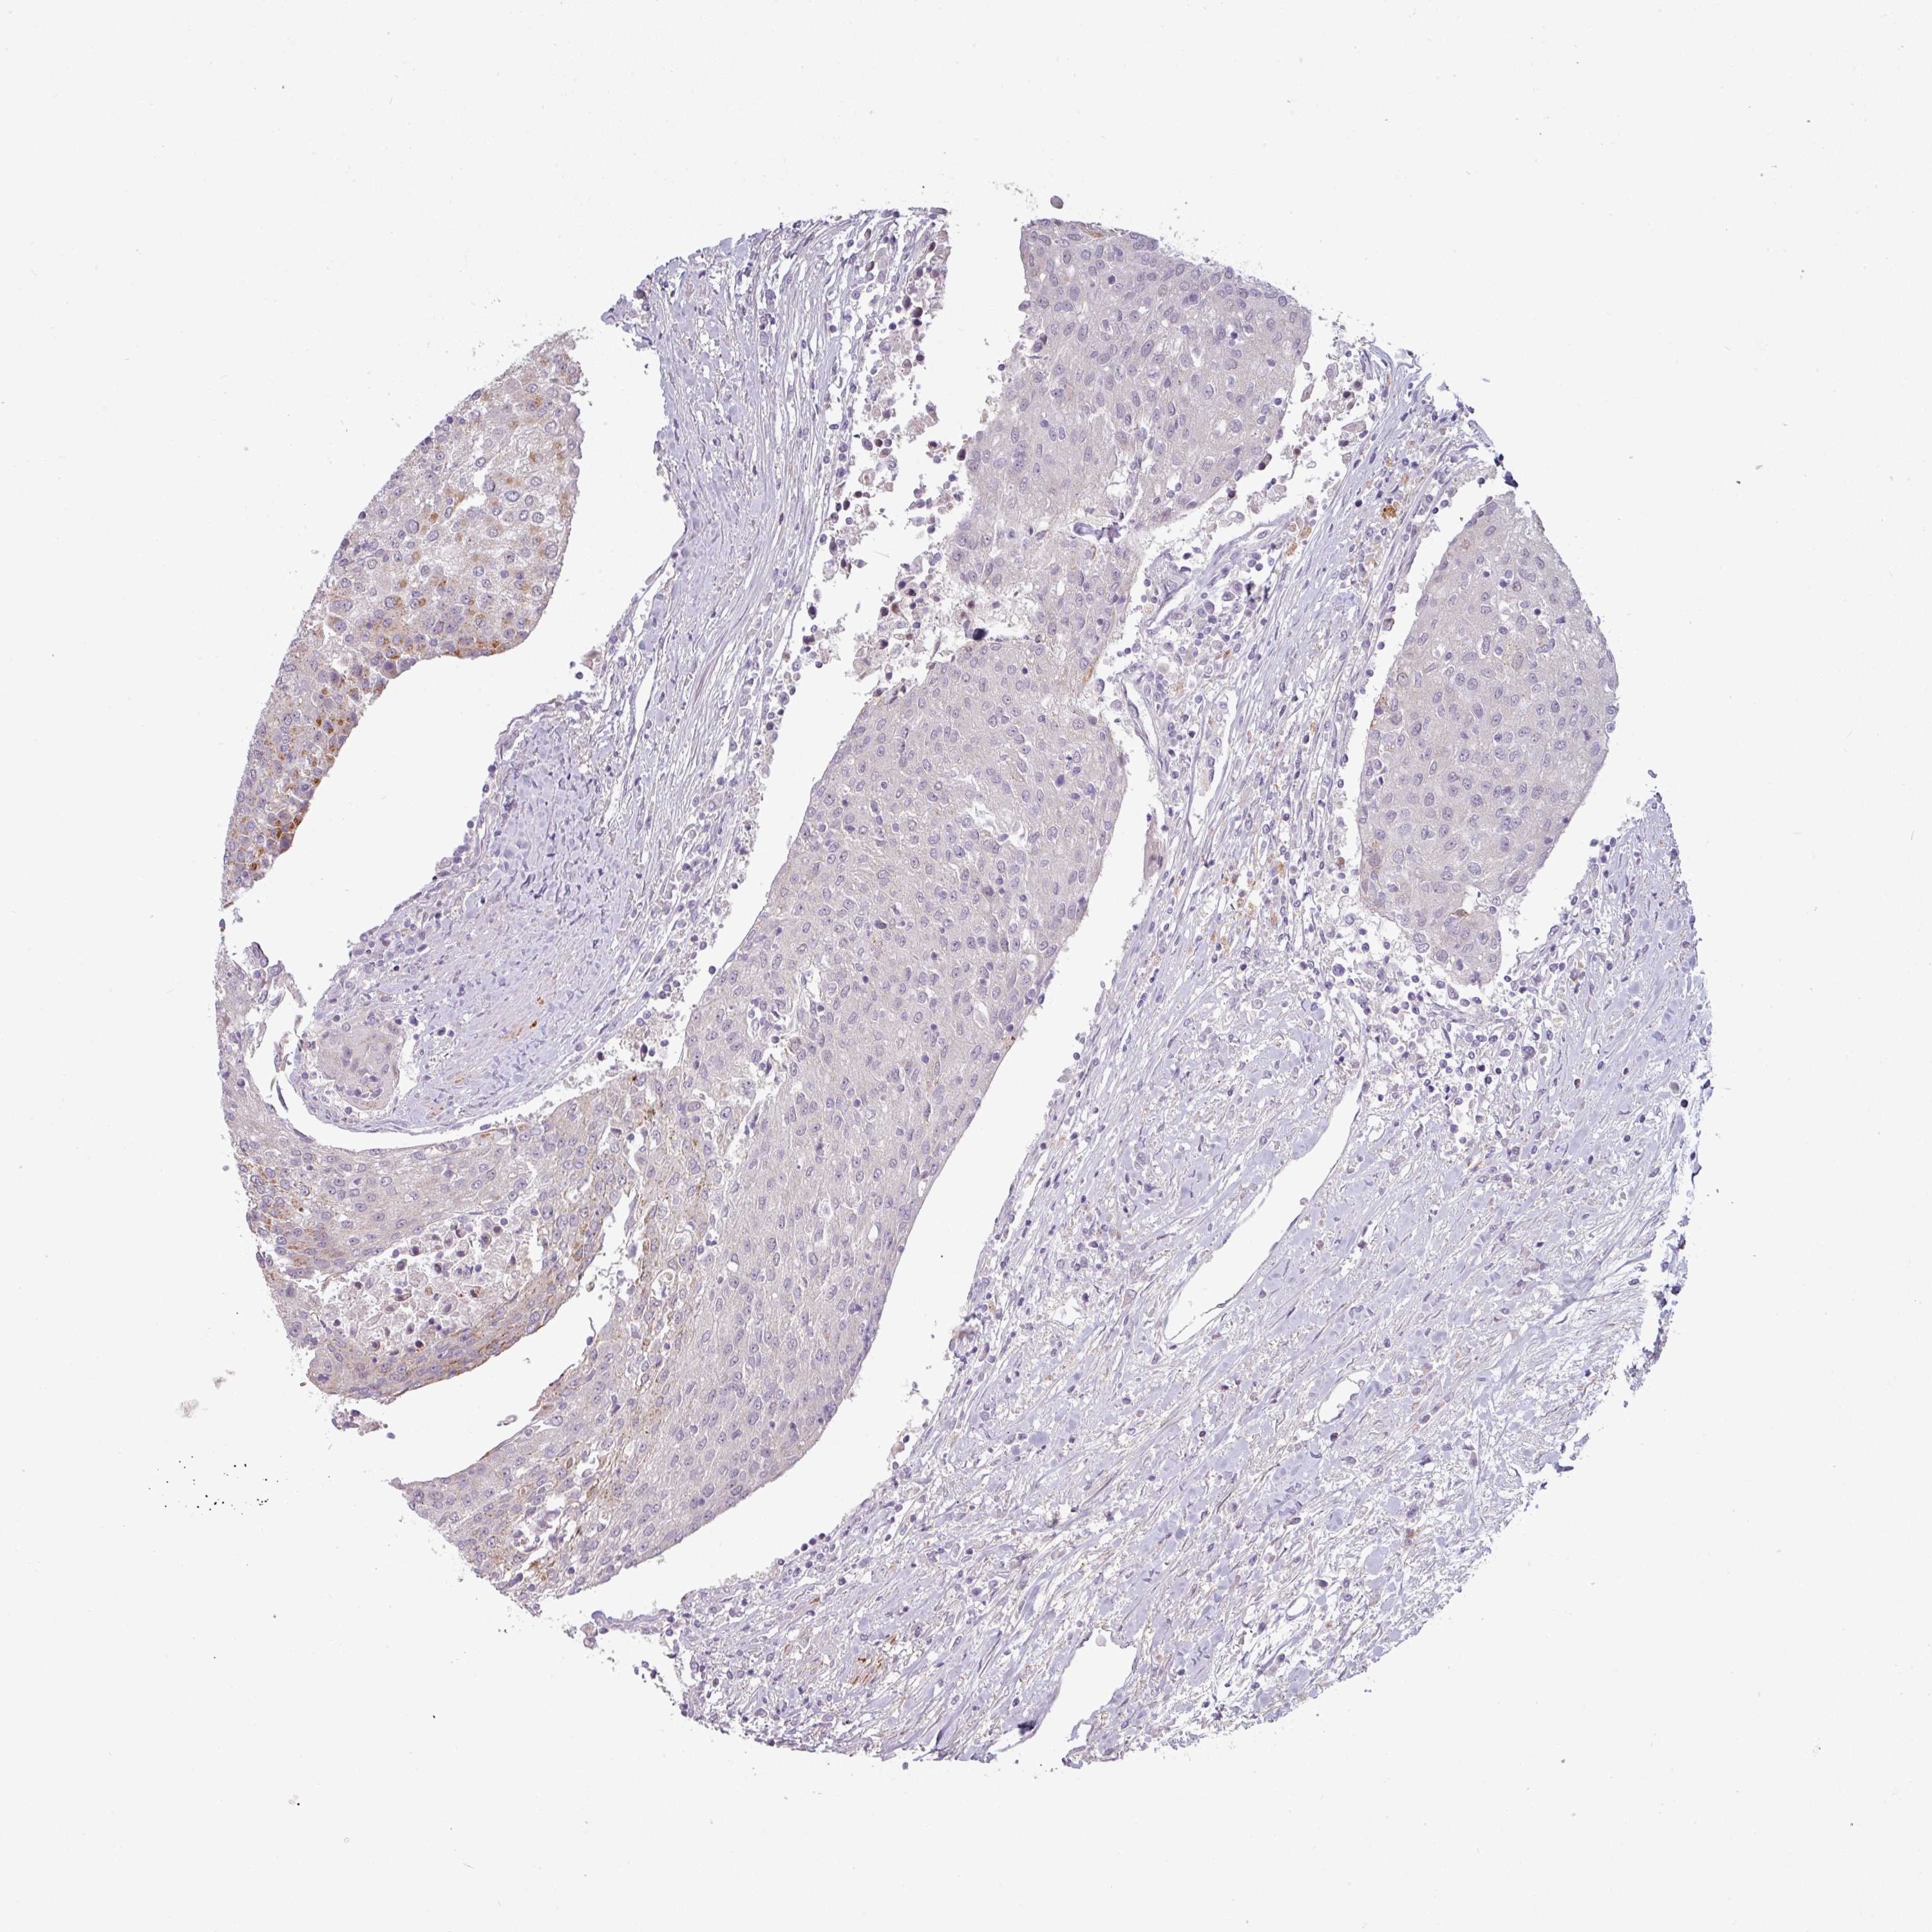

UROTHELIAL CANCER - Protein expressioni

A mouse-over function shows sample information and annotation data. Click on an image to view it in a full screen mode. Samples can be filtered based on level of antibody staining by selecting one or several of the following categories: high, medium, low and not detected. The assay and annotation is described here.

Note that samples used for immunohistochemistry by the Human Protein Atlas do not correspond to samples in the TCGA dataset.

Antibody stainingi

Antibody staining in the annotated cell types in the current human tissue is reported as not detected, low, medium, or high, based on conventional immunohistochemistry profiling in selected tissues. This score is based on the combination of the staining intensity and fraction of stained cells.

Each image is clickable and will lead to virtual microscopy that enables deeper exploration of all samples and also displays staining intensity scores, fraction scores and subcellular localization as well as patient and tissue information for each sample.

Antibody HPA052136

Antibody HPA056962

Staining

High

Medium

Low

Not detected

Intensity

Strong

Moderate

Weak

Negative

Quantity

>75%

75%-25%

<25%

None

Location

Nuclear

Cytoplasmic/membranous

Cytoplasmic/membranous,nuclear

Urothelial carcinoma, High grade

Urothelial carcinoma, Low grade

Urothelial carcinoma, NOS